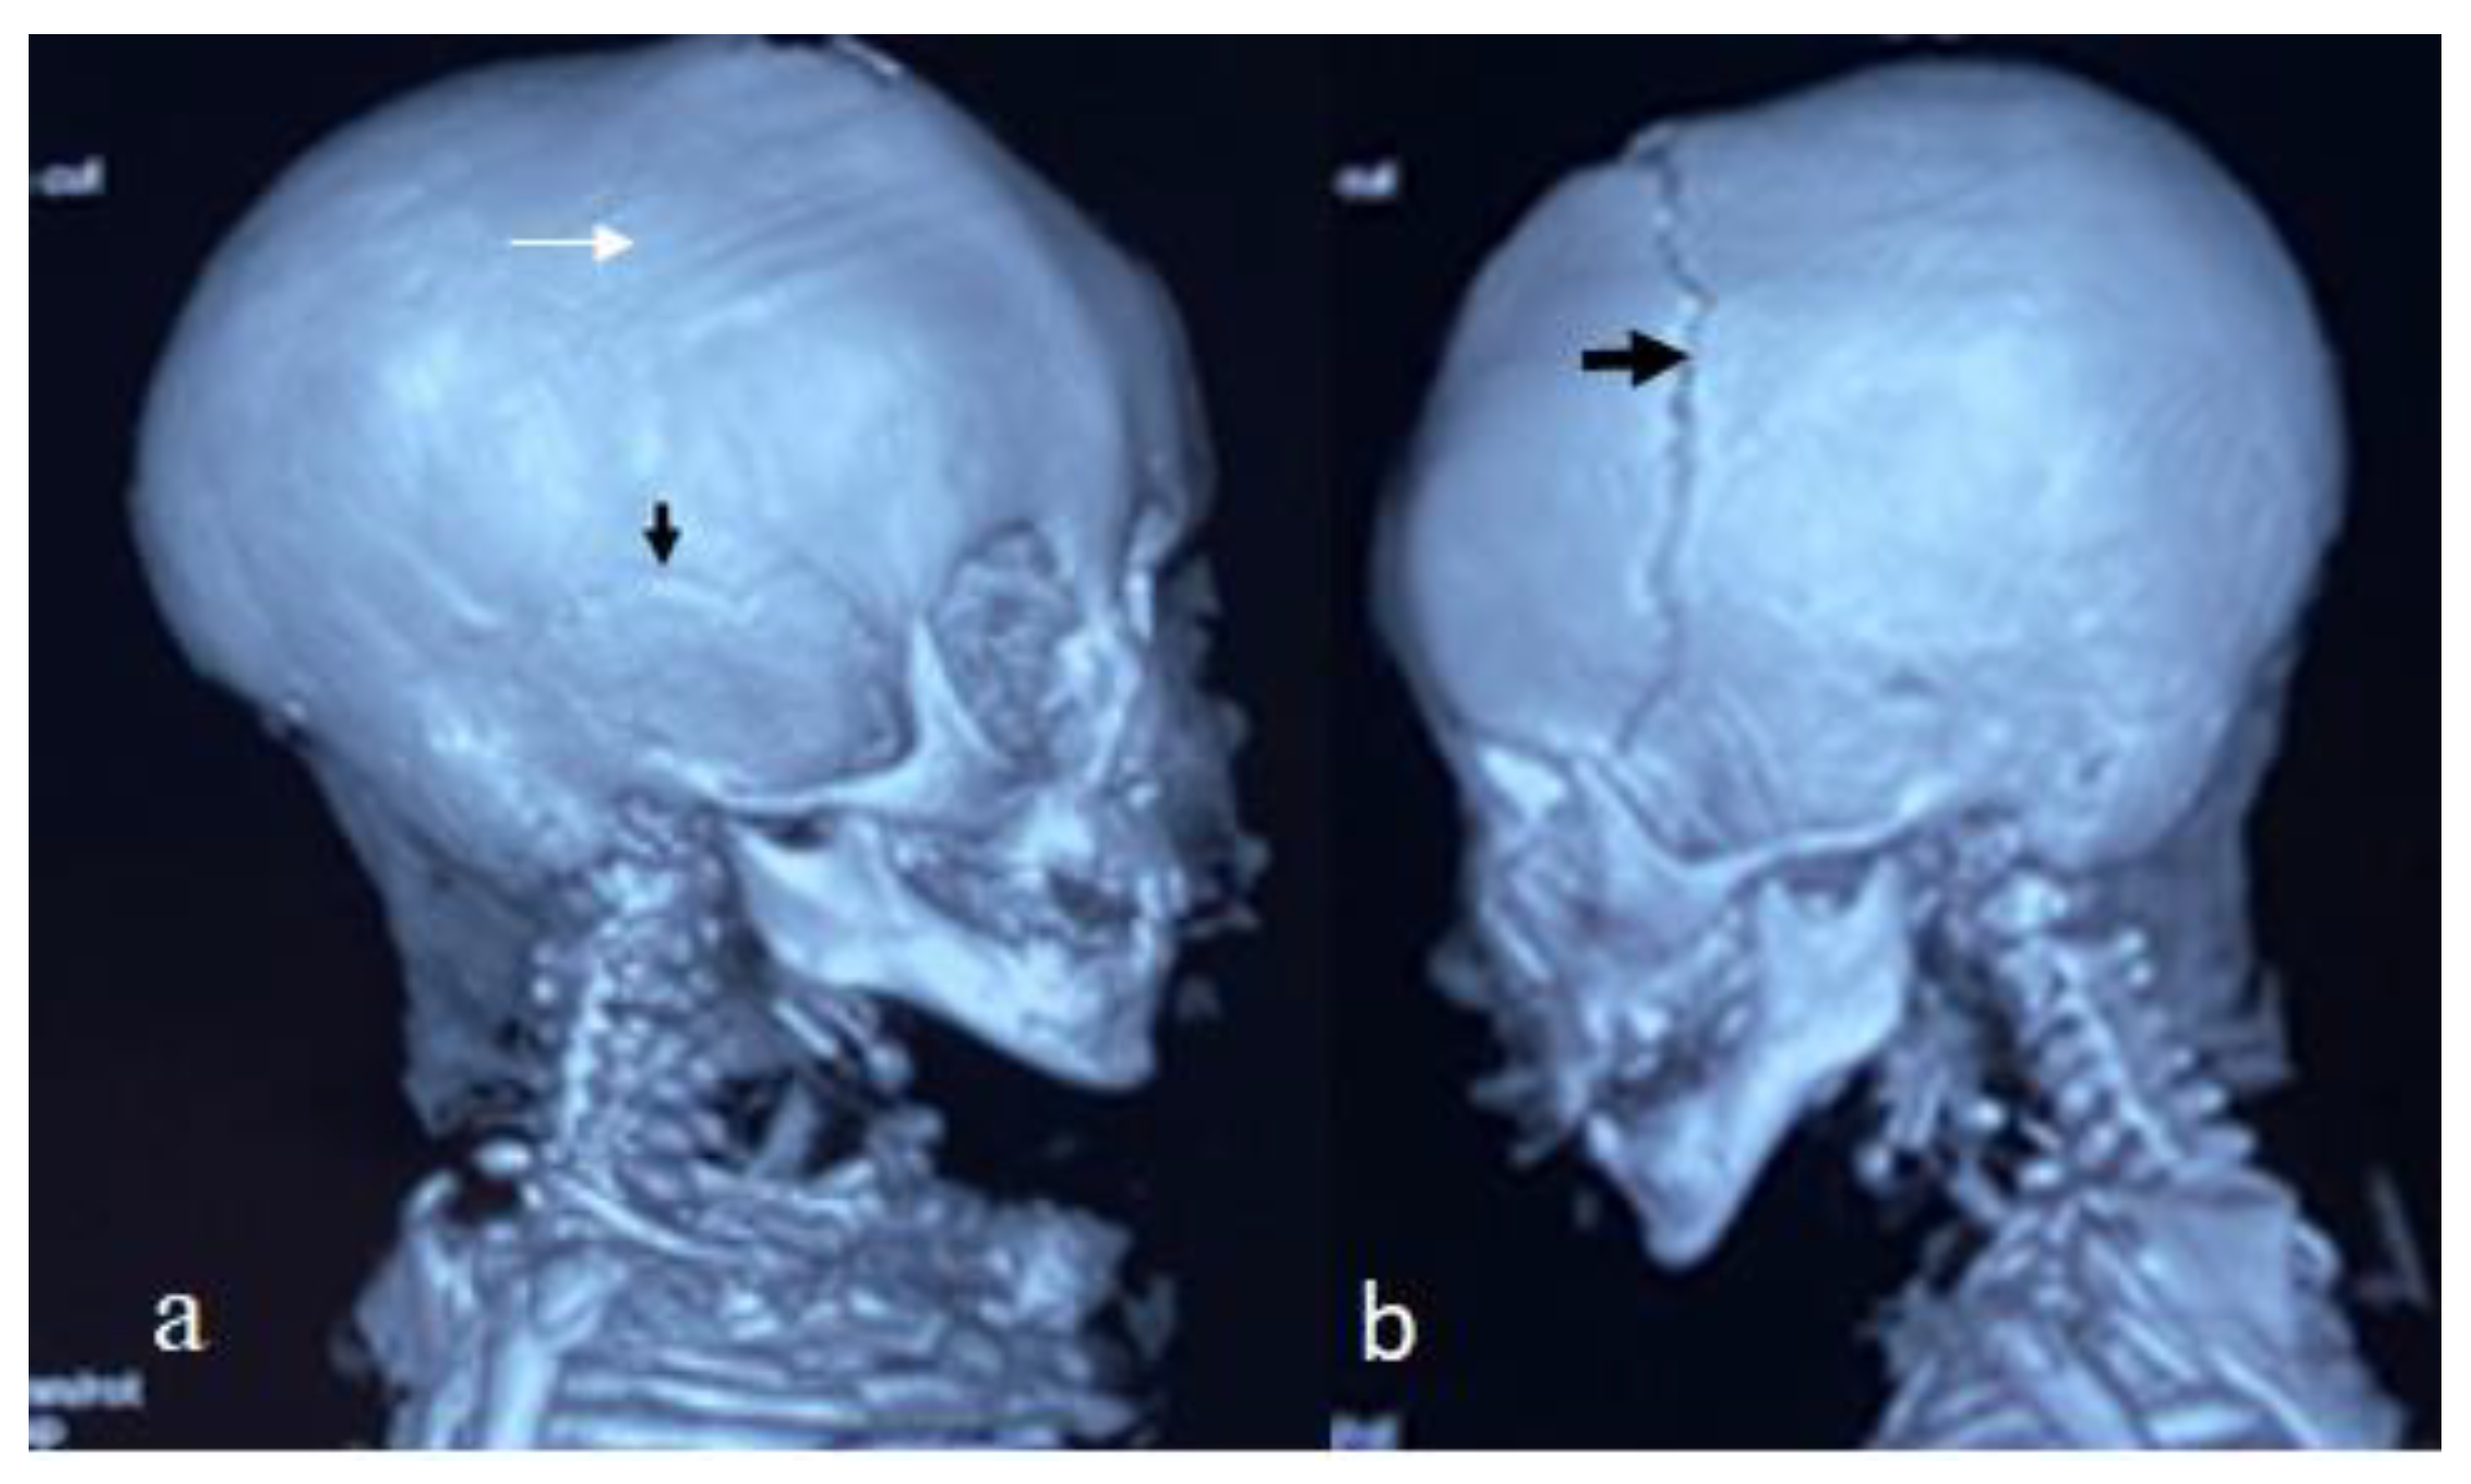

For this syndrome, we clinically investigated two unrelated affected boys. The first was a one-month-old boy presenting with multiple contractures who was falsely diagnosed in other institutes as having positional plagiocephaly associated with idiopathic multiple contractures. A clinical examination at the age of one month showed growth deficiency (-2SD) and OFC (around the 75th percentile). Clinically, he manifested an abnormal craniofacial contour with prominent sloping of the frontal area. The helices were over-folded. The palpation of the skull gives the impression of a newly formed ridge along the metopic suture and a newly formed ridge along the sagittal suture, with a feeling of a rudimentary anterior fontanelle (the skull is elongated from front to back). The musculo-skeletal examination showed ligamentous hyper laxity but not hypotonia. Multiple contractures over the upper and lower limbs were, respectively, associated with multiple dislocations (hips and knee joints). Skeletal survey: a general skeletal radiograph at the age of one month showed multiple malformation complex, starting from the skull and extending downwards to involve the upper and lower limbs, respectively. The skull showed an apparent synostosis of the metopic suture. The upper limbs and lower limbs were notably associated with multiple dislocations (hips, wrists, knees and ankle, in addition to camptodactyly at the interphalangeal joints). The limb abnormalities were diagnostically important, in that there was a complete anterior dislocation of the tibia and fibula, and the patellae were absent (Figure 1a). A sagittal cranial CT scan showed craniosynostosis of the metopic suture associated with a well- formed ridge spreading from the metopic suture to involve the anterior portion and the posterior part of the sagittal suture, associated with the obliteration of the anterior fontanelle, with the eventual development of scaphocephaly (Figure 1b). The second child is a 12-month-old-boy- presenting with multiple dislocations on top of a malformative craniosynostosis. He manifested apparent craniofacial dysmorphic features (facial asymmetry, proptosis, depressed nasal bridge, long philtrum and a low set malformed ears). An AP skull radiograph at the age of 12 months showed an early closure of the metopic (black arrow head) and sagittal sutures (white arrow head) and partial closure of the right coronal suture (white arrow), leading to the development of skull–crown asymmetry. A 3D reconstruction CT scan of the same child at the age of 14 months showed a well-defined palpable bony ridge (black arrow) extending from the metopic suture upwards to include the sagittal suture (white arrow) (Figure 2a). Note that the extremely large orbital cavities (arrowhead) with diffuse early closure of the metopic and the sagittal sutures (arrow), leading to the development of a dysmorphic and asymmetrical contour of the head because of the unilateral upward bulging of the crown (white arrow). Asymmetrical contour of the cranium resulted from the unilateral partial closure of the right coronal suture and simultaneous but asymmetrical early closure of the squamosal sutures (Figure 2b). A 3D reconstruction CT scan showed the disproportion in growth between the cranial and facial bones. The apparent closure of the metopic and sagittal sutures led to the development of scaphocephaly. Interestingly, there was a unilateral early closure of the right coronal (white arrow) and early closure of the squamosal sutures, respectively (black arrow), causing the development of asymmetrical bulging of the central part of the crown (Figure 3a). A 3D reconstruction confirmed the persistence of the left coronal suture (arrow—Figure 3b). Chromosomal karyotyping and the FISH test were normal, and there were no disease-causing copy number variations (CNV) using array-CGH analysis.

Figure 2. AP skull radiograph at the age of 12 months-old-boy- showed early closure of the metopic (black arrow head) and sagittal sutures (white arrow head) and partial closure of the right coronal suture (white arrow), leading to development of skull–crown asymmetry. Three-dimensional reconstruction CT scan of the same child at the age of 14 months showed a well-defined palpable bony ridge (black arrow) extending from the metopic suture upwards to include the sagittal suture (white arrow) (a); Note that the extremely large orbital cavities (arrowhead) with diffuse early closure of the metopic and the sagittal sutures arrow), leading to the development of a dysmorphic and asymmetrical contour of the head because of the unilateral upward bulging of the crown (white arrow). Asymmetrical contour of the cranium resulted from the unilateral partial closure of the right coronal suture with the simultaneously but asymmetrical early closure of the squamosal sutures (b).